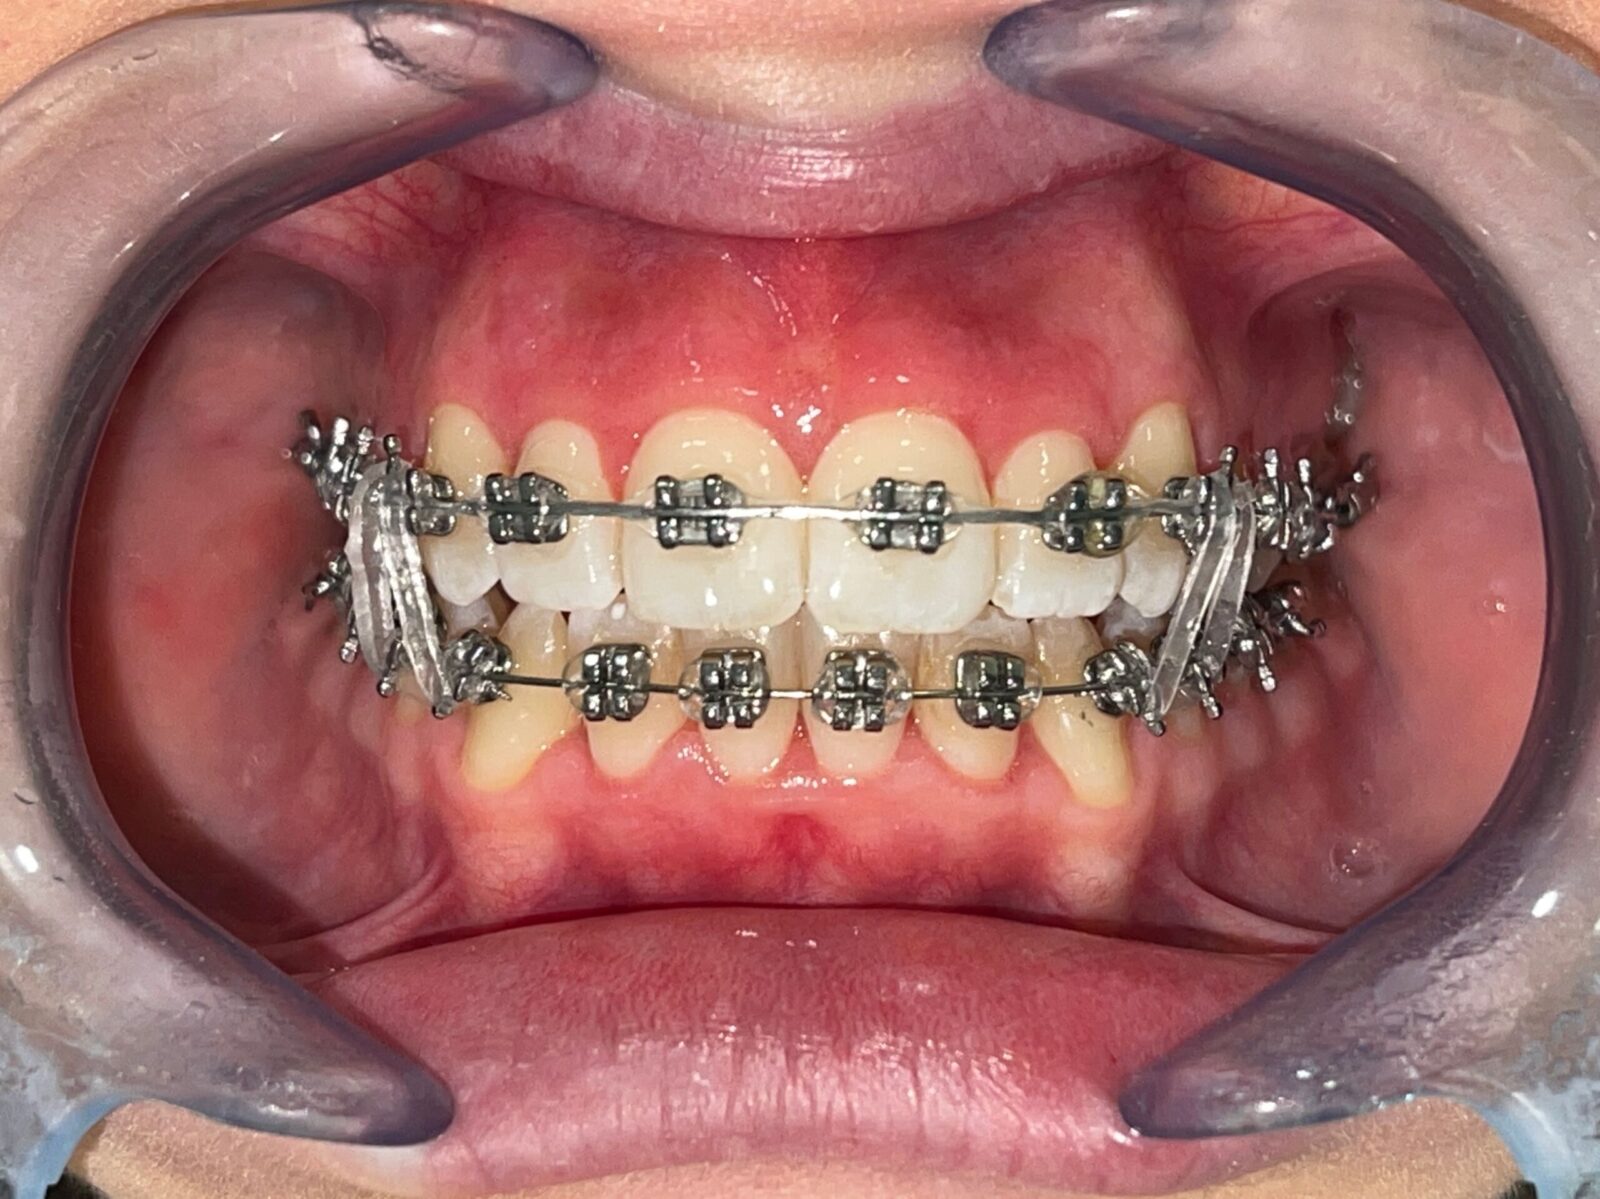

1. Apparecchi Ortodontici Fissi in Metallo

La soluzione classica e più efficace per riallineare i denti in modo stabile e preciso. Indicata per tutte le età e per casi complessi di malocclusione.